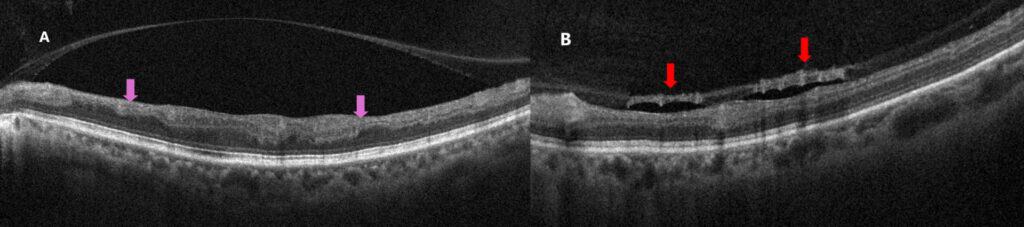

Figure 3: Optical coherence tomography (OCT) at the 2-year follow-up. A) OCT through the macula showing inner retinal thinning and disorganization (purple arrows). Partial posterior vitreous detachment is noted. B) OCT along the inferior temporal arcade showing pre-retinal neovascularization (red arrows) along the posterior hyaloid face.

Dilated fundus examination of the left eye revealed venous attenuation and sheathing in the inferior temporal arcade. A pre-retinal neovascular frond was noted along the inferior temporal arcade, and a smaller area of retinal neovascularization was noted approximately 1 disc-diameter inferior to the optic nerve head. Collateralization and telangiectasias were appreciated within the inferior macula. No hemorrhages or cotton-wool spots were noted. There was sectoral pallor of the inferior aspect of the optic nerve head with an optociliary collateral vessel. The right eye was unremarkable.

OCT imaging revealed inner retinal thinning and disorganization, particularly within the inferior macula. The outer retinal layers and the ellipsoid zone appeared intact, with no macular edema (Fig. 3). Pre-retinal neovascularization was noted along the posterior hyaloid face at the inferior temporal arcade. This was confirmed by OCT-A (Fig. 4).